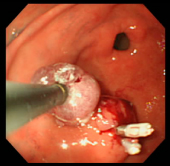

| 症例(胃ポリープ切除1) | |||

| ポリープ | 根元に生理食塩水を注入して水ぶくれ状態をつくり、膨らんだその部分に スネアをかけて高周波の電流を流し病変部を焼き切っている状態。 |